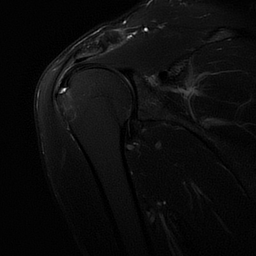

MRI

focal non-transmural articular-sided defect of fluid signal intensity of the rotator cuff on fat-saturated T2- weighted or intermediate-weighted images with intact residual fibres